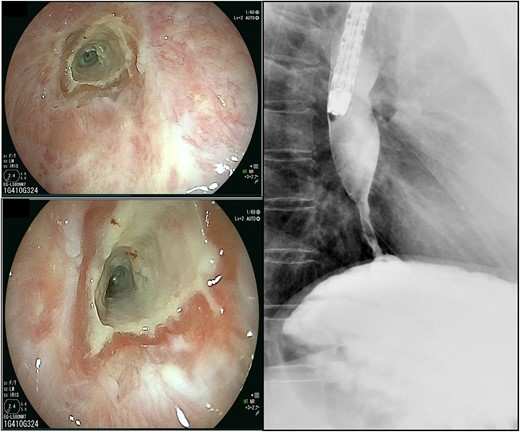

The scars continued down the esophagus, extending beyond 23 cm from the incisors, while the lower esophagus to the gastroesophageal junction was severely constricted.